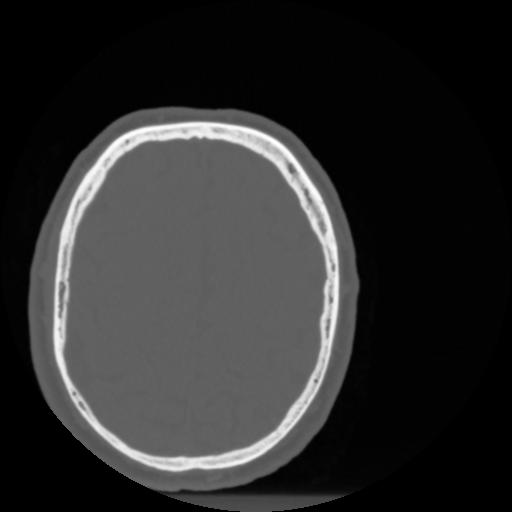

4 CEREBRO,,Vol,0.5,CEREBRO,,